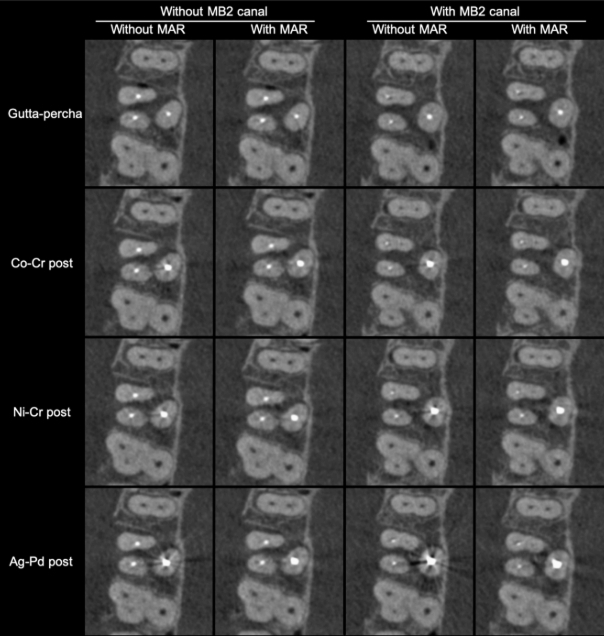

Экспериментальные группы формировались путем сканирования каждого зуба 8 раз — с активацией и без активации инструмента MAR, а также с четырьмя типами внутриканальных материалов в небном корне:

• гуттаперча,

• металлические штифты из серебряно-палладиевого сплава (Ag-Pd),

• никель-хромового сплава (Ni-Cr),

• кобальто-хромового сплава (Co-Cr) (см. рис. 2).

В результате было получено всего 320 КЛКТ-объёмов (40 зубов × 2 условия MAR × 4 внутриканальных материала). Металлические штифты имели длину 20 мм и соответствовали по толщине используемому эндодонтическому инструменту.

РИСУНОК 2 – Аксиальные срезы КЛКТ, демонстрирующие наличие или отсутствие канала MB2 при использовании различных внутриканальных материалов, с активацией и без активации инструмента MAR.